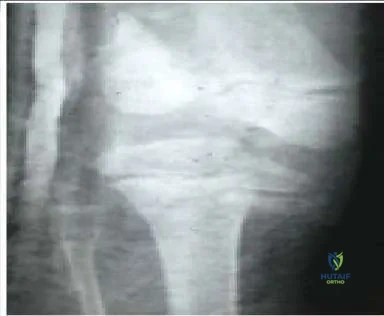

A 12-year-old boy twisted his knee while riding a bicycle. Based on his radiographs (Slide), which of the following is the most appropriate diagnosis:

Orthopedic Prometric Exam Chapter 3 Image

Explanation

This patient has a tibial spine avulsion, classified as type III by McKeever and Meyers. Treatment options include closed immobilization or arthroscopic or open reduction and internal fixation.